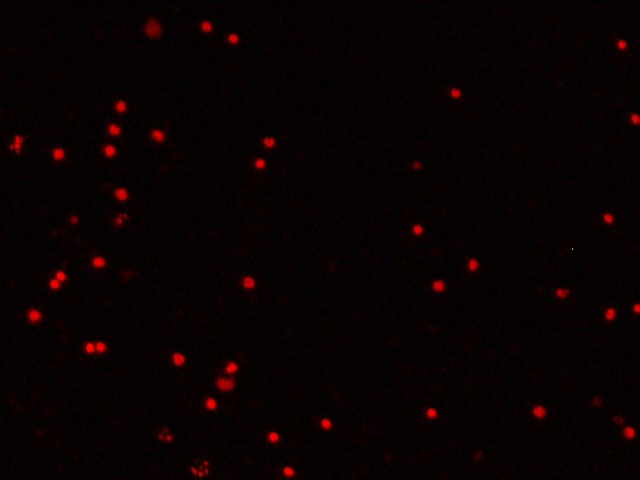

После введения цитопротекторов в лунки с лейкоцитарной взвесью пациентов с ИБС в «терапевтической концентрации» обнаружили два варианта изменения индекса жизнеспособности – в виде его повышения либо снижения, что зависело от исходных показателей анализа крови больных. О цитопротекторном эффекте препарата судили исключительно в случае повышения индекса жизнеспособности, т. е. при увеличении количества живых клеток и уменьшении количества мёртвых клеток в полях зрения (рисунок 3).

Б1. Мёртвые клетки в исходном состоянии | Б2. Мёртвые клетки после введения |

Fig. 3. Cytoprotective effect of the drug (fluorescence microscopy, 200× magnification)

А1 и А2 – увеличение количества живых клеток в поле зрения после введения цитопротекторного препарата (триметазидина или этоксидола) (окраска Сalcein АМ);

Б1 и Б2 – уменьшение количества мёртвых клеток в поле зрения после введения цитопротекторного препарата (триметазидина или этоксидола) (окраска Ethidium bromide).